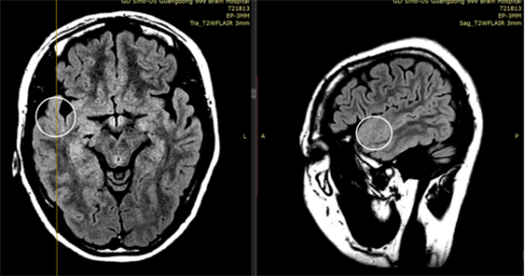

患者入院后,庄君为她安排了长程视频脑电监测。在检查中,多次记录到患者的“跳舞样”发作:临床上摇头、挥手的同时,脑电图显示右侧大脑,尤其是右侧中央—顶—颞区棘波节律性演变,随后双侧半球同步性电压低减,然后出现舞蹈样动作。MRI提示右侧颞极皮层轻度异常,PET也显示该区域代谢减低,进一步锁定了“问题源头”的范围。神经心理评估发现,患者已出现轻度认知受损。

患者MRI提示:圆形眶内可见右侧颞极局灶性皮层发育不良(FCD)

患者pet检查提示:可见圆形眶内显示右侧颞极低代谢